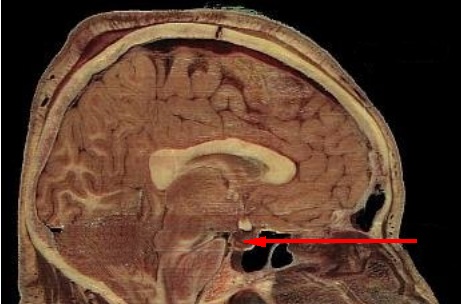

– La hipófisis se encarga de producir y secretar diferentes hormonas que participan de la regulación del crecimiento, la reproducción y el metabolismo.